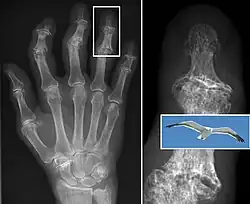

In smaller joints, such as at the fingers, hard bony enlargements, called Heberden's nodes (on the distal interphalangeal joints) or Bouchard's nodes (on the proximal interphalangeal joints), may form, and though they are not necessarily painful, they do limit the movement of the fingers significantly. Osteoarthritis of the toes may be a factor causing formation of bunions,[16] rendering them red or swollen.

Bone (left) and clinical (right) changes of the hand in osteoarthritis